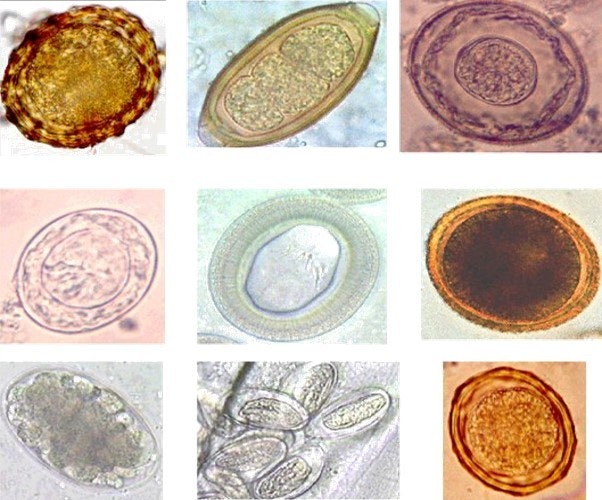

Микрофотографии яиц гельминтов Toxocara canis

Раздел: Фотоэссе